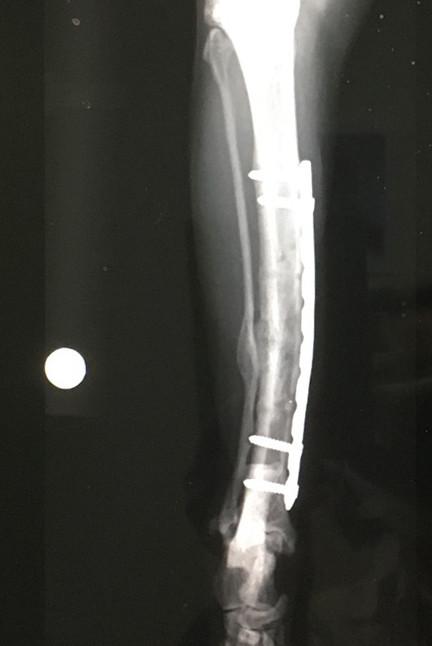

7月17日 手術から 12ヶ月 後

2回目のプレート抜去

メインプレートとボルト4本抜去。